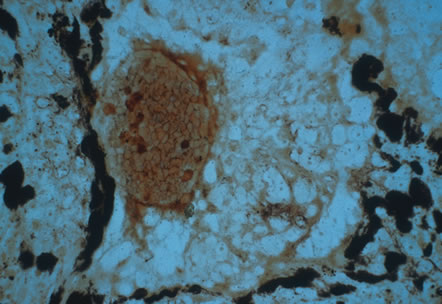

In primary ocular HSV infections, a severe follicular conjunctivitis with regional adenopathy is present. Vesicles may appear on the eyelid skin or lid margin, producing blepharitis (Fig. 3). Corneal involvement initially takes the form of a superficial punctate keratitis, which may progress to dendritic or geographic ulceration. Stromal infiltrates and uveitis are less common and relatively mild in primary disease. In uncomplicated cases, lesions usually heal completely in 2 to 3 weeks without scarring. Most cases of ocular HSV are recurrences. Recrudescent ocular herpes may take the form of dendritic or geographic ulcers, recurrent erosions, interstitial or disciform stromal keratitis, and anterior uveitis.3 HSV may also be an agent of retinitis and acute retinal necrosis (Fig. 4).